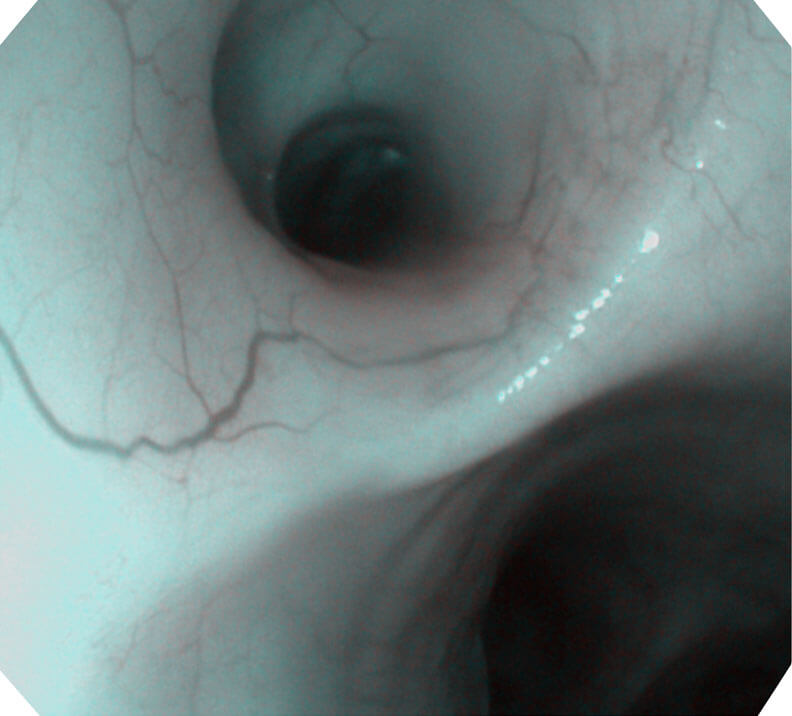

帮助医生更加清晰地观察气管表面病灶

120°视场角,满足更大视野范围的观察。配合 VIST 染色,助力呼吸系统疾病的诊断。

光电复合染色成像技术(VIST)是一种光学滤波和数字滤波相结合的染色成像技术,摒弃了滤光转轮而直接采用光谱组合的方案,加入了血红蛋白吸收高峰与次高峰的蓝紫光和绿光光谱,更有利于黏膜血管吸收,突显浅表层血管和中层血管的对比度,因而具备更高的图像对比度,有助于观察微细结构变化及病灶边界的观察。